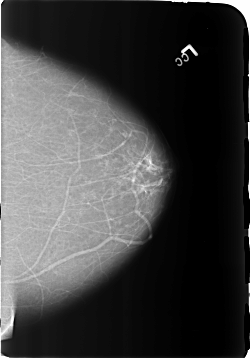

B_3172_1.LEFT_CC

LEFT_CC LINES 5728 PIXELS_PER_LINE 3992 BITS_PER_PIXEL 12 RESOLUTION 50 NON_OVERLAY